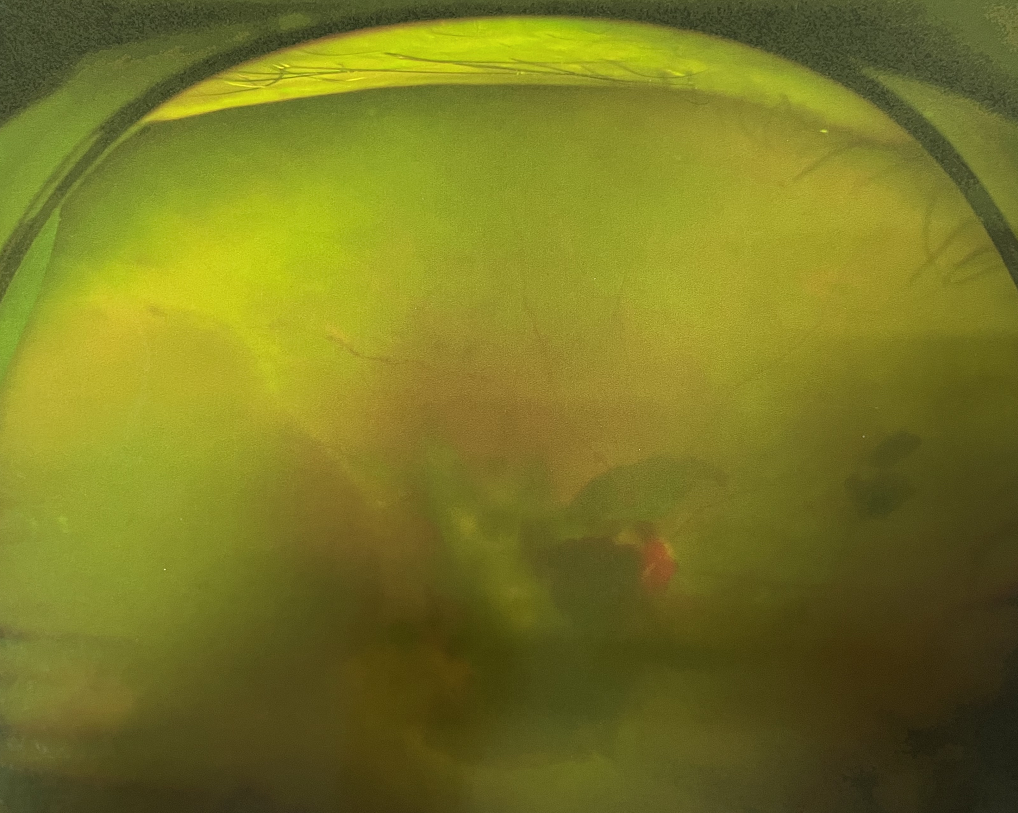

眼底出血是指眼內(nèi)視網(wǎng)膜出血,或玻璃體內(nèi)出血。眼底位于眼睛深處,所以這類出血只靠肉眼是看不到的,早期可能不紅、不痛、不癢,需通過專業(yè)的眼底檢查才可看到,往往短期內(nèi)就可造成視力驟降甚至失明!

同樣的,眼底出血也是一種癥狀,而非病種。誘發(fā)眼底出血的原因很多,常見的有全身性血管病和血液病、視網(wǎng)膜血管異常、機(jī)械性阻塞、炎癥性疾病或免疫復(fù)合物侵犯血管壁等。

一只眼睛眼底出血